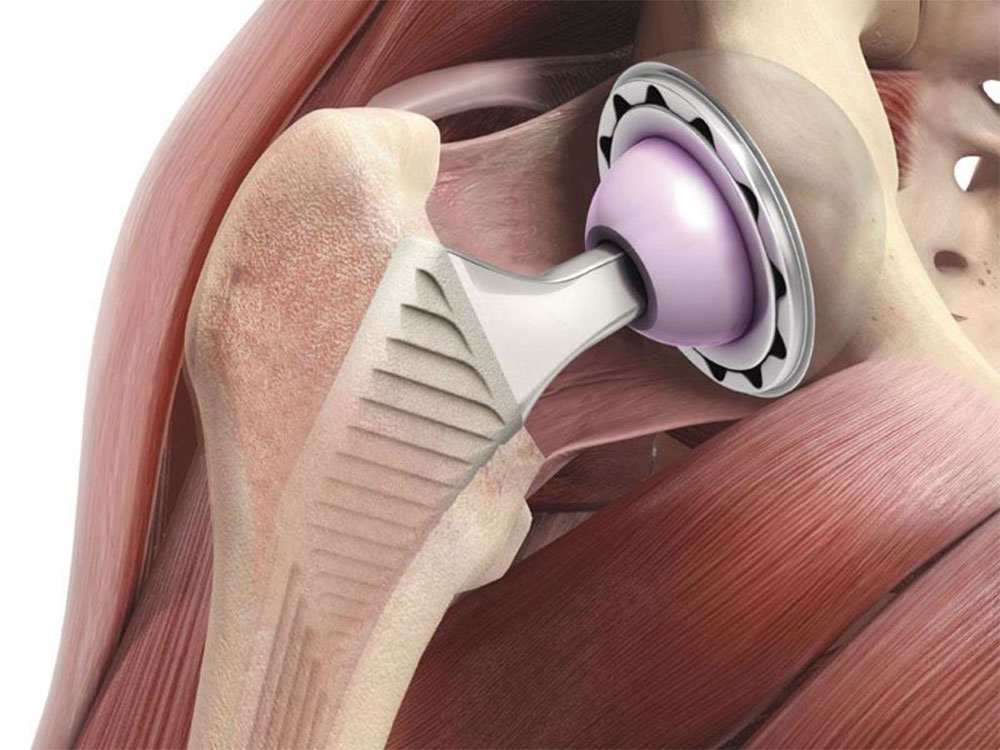

Эндопротезирование тазобедренного сустава: фото и схемы